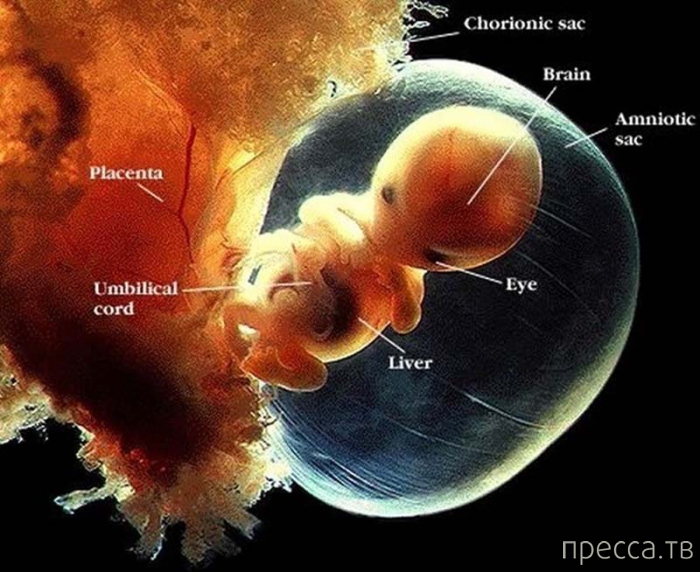

2. 5-6 недель беременности.

Несмотря на то, что плод достиг лишь 6 мм в длину, ее (в данном случае, мы говорим о девочке) нос, рот и ушки уже начинают формироваться. Ее сердце бьется около 100 раз в минуту (почти в два раза быстрее сердца матери), а кровь начинает циркулировать по телу. Мозговые волны различимы уже в 2-3 недели!

3. Седьмая неделя беременности. По часовой стрелки, начиная с 12: Хорионический мешочек, мозг, амниональный мешочек, глаз, печень, пуповина, плацента.

2. 5-6 недель беременности.

Несмотря на то, что плод достиг лишь 6 мм в длину, ее (в данном случае, мы говорим о девочке) нос, рот и ушки уже начинают формироваться. Ее сердце бьется около 100 раз в минуту (почти в два раза быстрее сердца матери), а кровь начинает циркулировать по телу. Мозговые волны различимы уже в 2-3 недели!

3. Седьмая неделя беременности. По часовой стрелки, начиная с 12: Хорионический мешочек, мозг, амниональный мешочек, глаз, печень, пуповина, плацента.